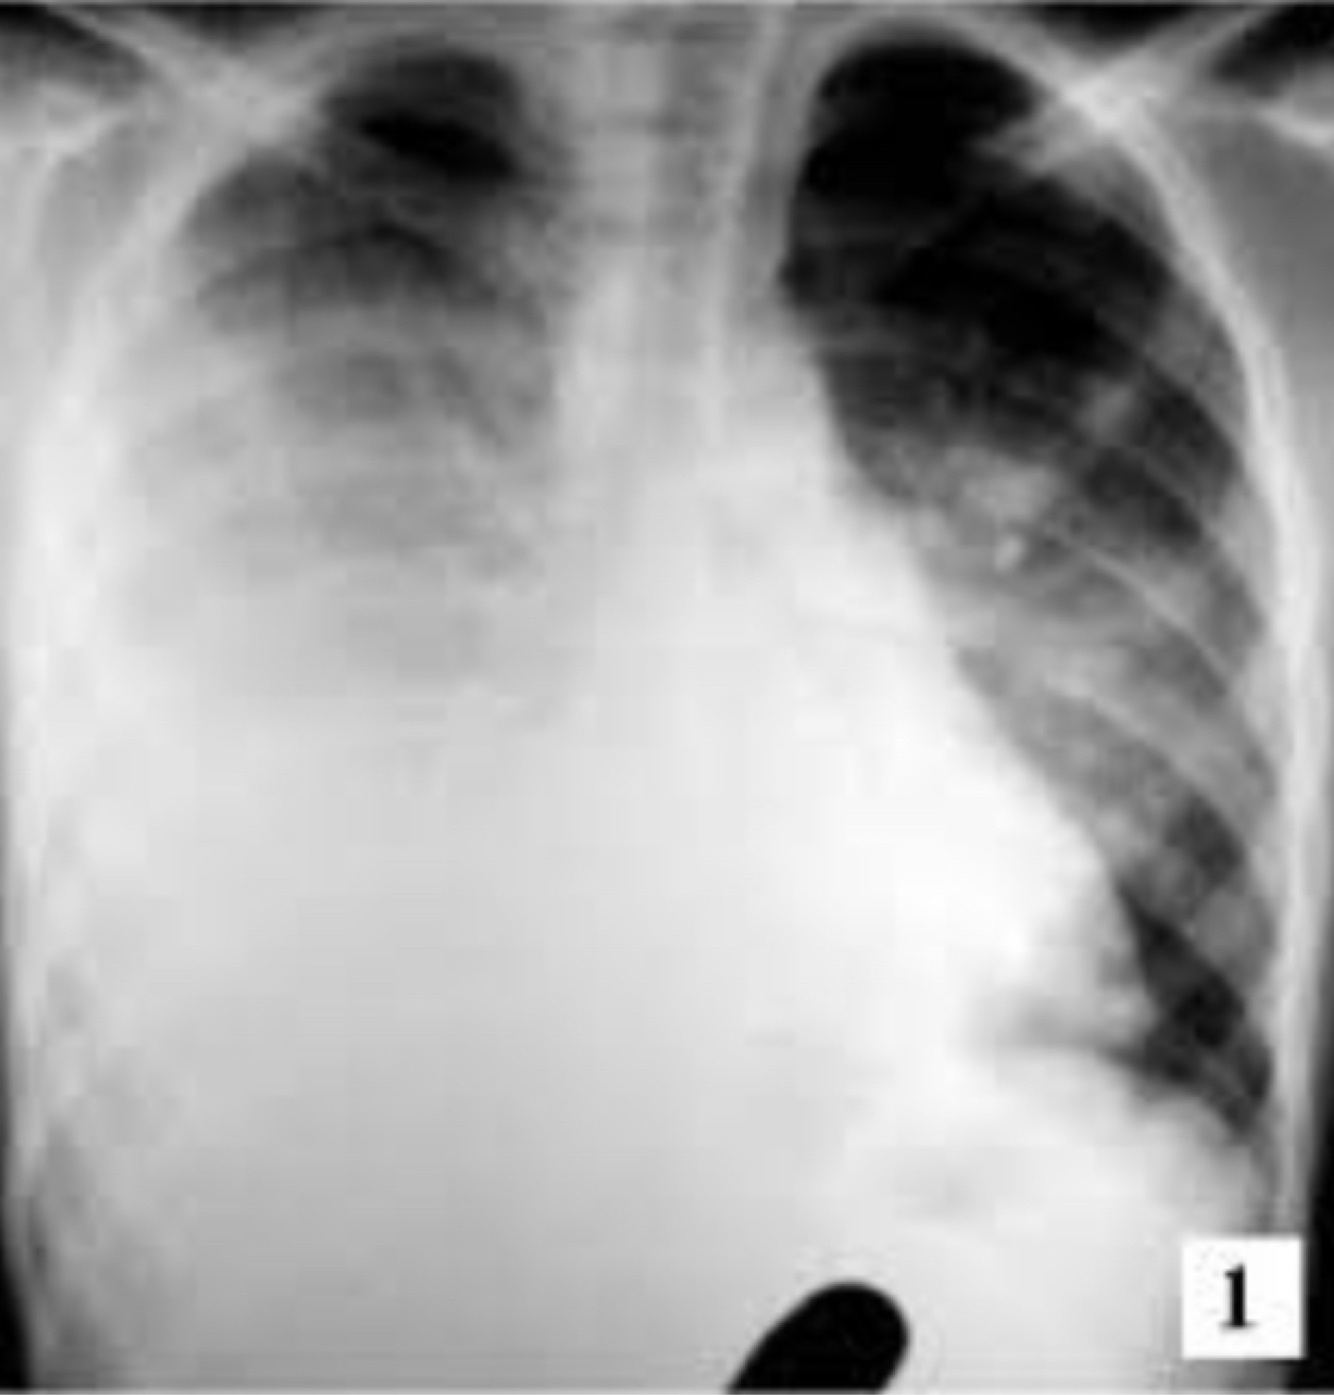

Signos de derrame pleural:

A

• Disminución de amplexión y amplexación

• Ruidos respiratorios ausentes

• Mate, submate

derrame pleural